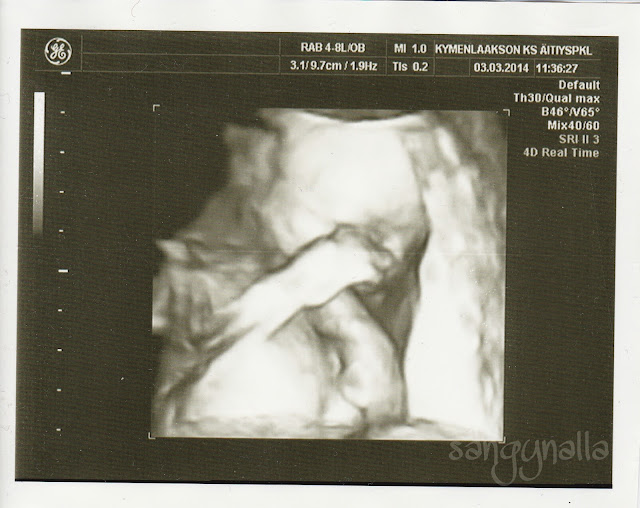

Rakenneultraa odotimme taas malttamattomina, puoliskoni halusi ehdottomasti tietää kumpi meille tulee, minä taas ehdottomasti en halunnut. Rv20+4 matkasimme taas Kotkaan. Vauveli sai painoarvion 396g. Tällä kertaa 3D kuvista oli enemmän iloa kuin niistä tavallisista. Np:n 3D:ssä näkyy vain pieni pahkurainen hahmo, nyt saimme kuvan jos vauvelimme peittää kasvojaan kädellä ja aukoo suutaan ja sulattaa meidän sydämemme aivan täysin edelleen kuvia katsoessa. Ja kyllä myös sulattaa joka kerta kun työntää jalkojaan mun kyljestä läpi tai kun puskee koko pienellä vartalollaan vatsaani milloin minkäkin näköiseksi palikaksi.